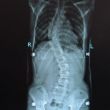

Scoliose